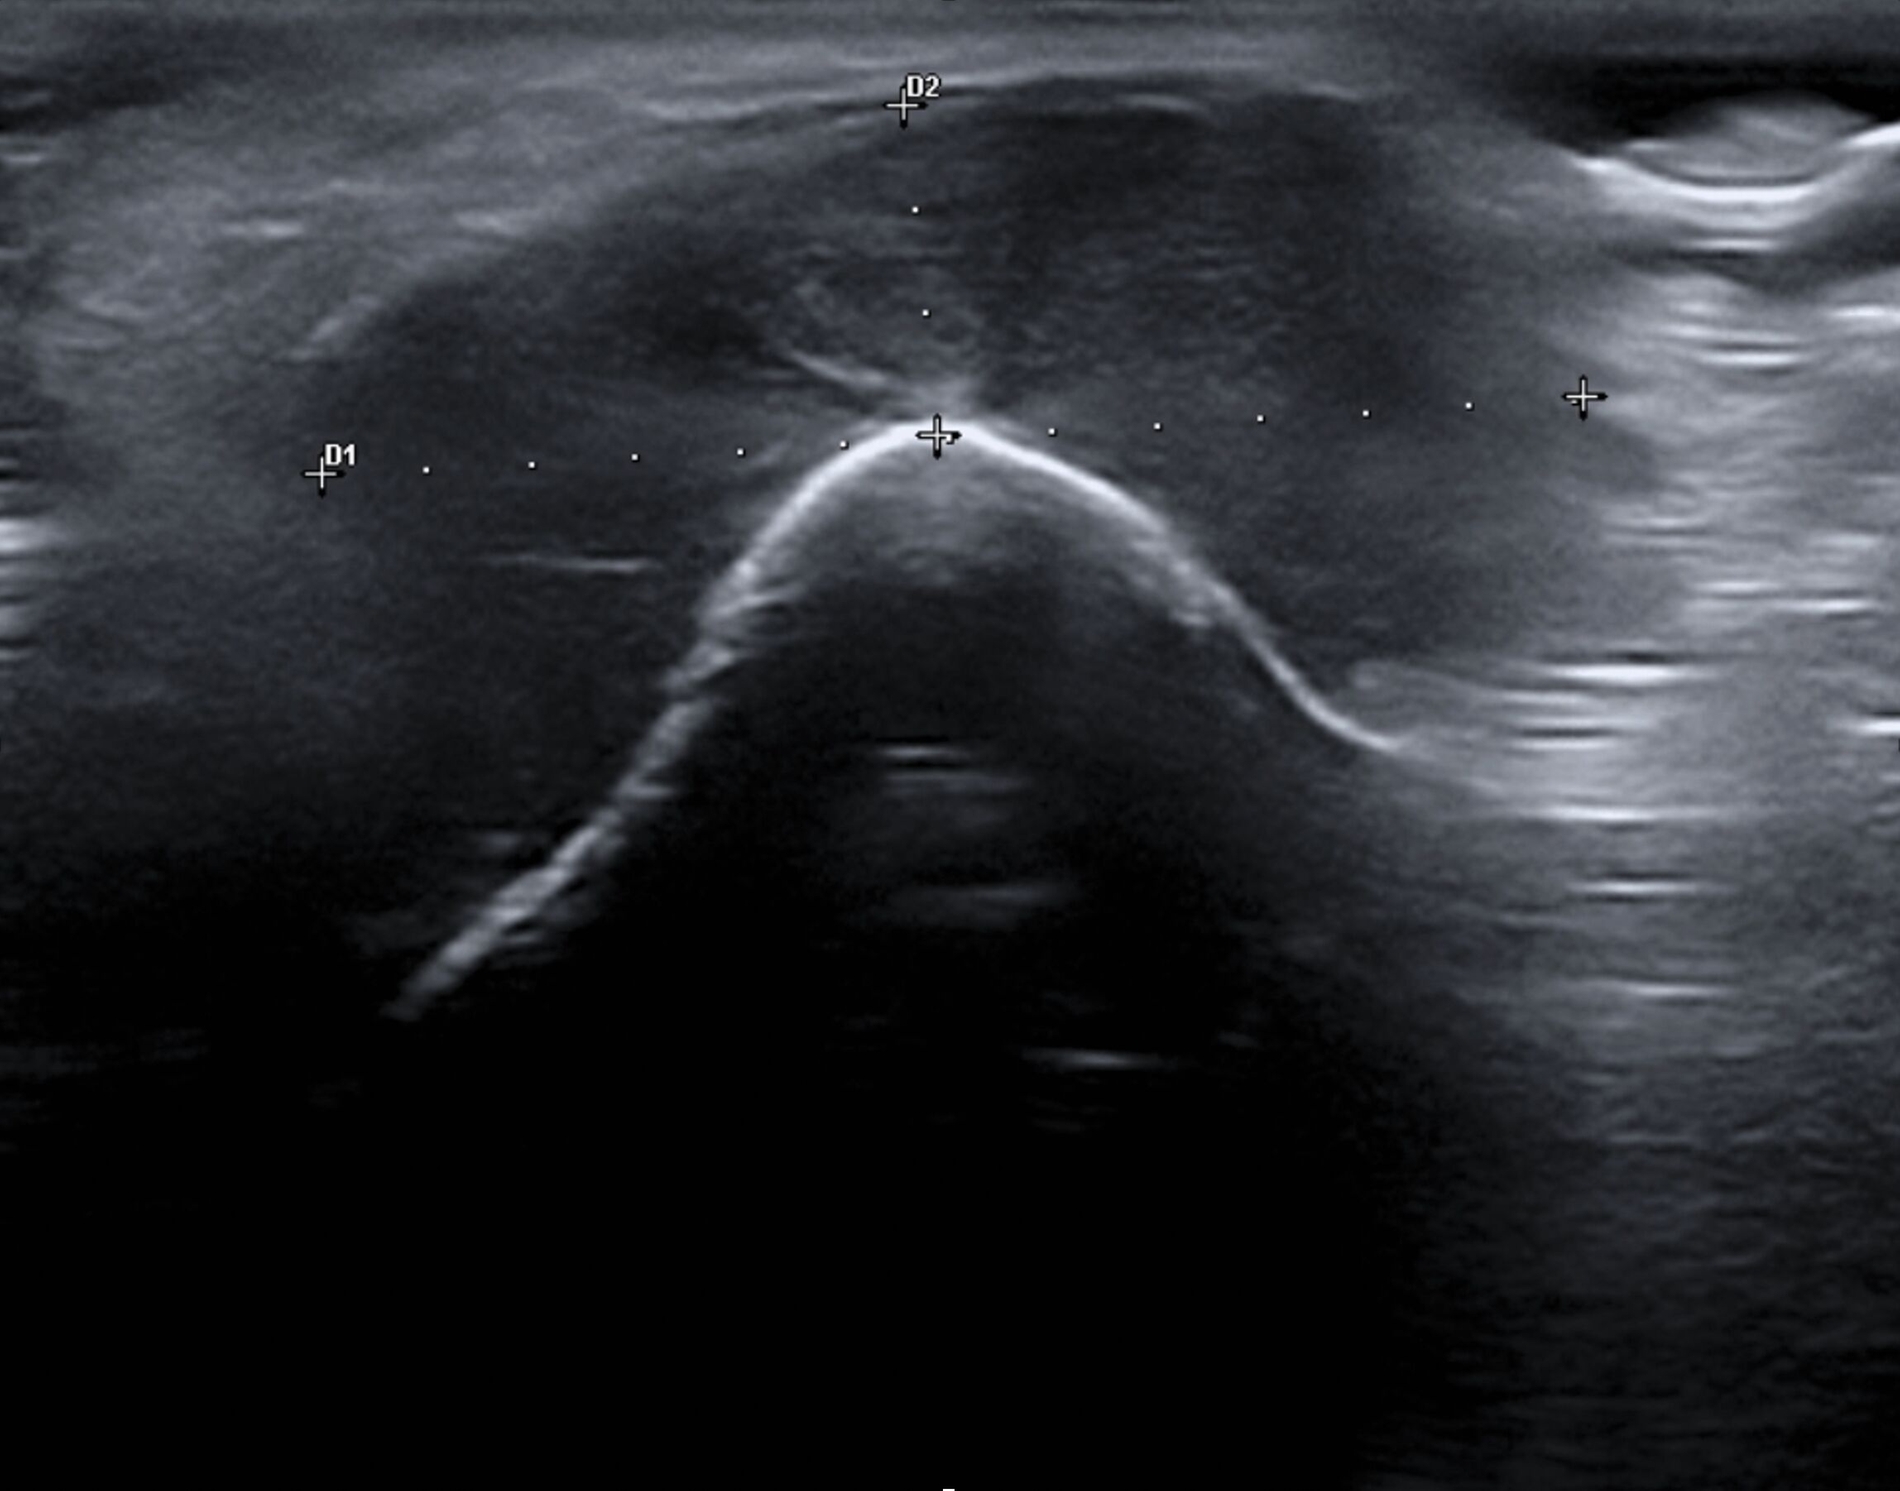

Aufgrund einer Größenprogredienz des Befunds mit inzwischen auch ästhetischer Einschränkung wurde schließlich doch eine Vorstellung bei einem MKG-Chirurgen empfohlen, um die Abklärung der Raumforderung zu initiieren. Klinisch zeigte sich ein derb palpabler, nur teilweise verschieblicher Befund im Bereich des rechten Kinns (Abbildung 1). Weitere Auffälligkeiten oder Hautbefunde kamen nicht zur Darstellung. Sonografisch imponierte ein konzentrisches Muster aus echoarmen und echoreichen Schichten (Abbildung 2).

Eine Unterbrechung der Kortikalis oder Abszessformationen ergaben sich nicht. Zur erweiterten Diagnostik erfolgte die Anfertigung einer Magnetresonanztomografie des Kopf-Hals-Bereichs. Hier zeigte sich bildmorphologisch ein zur Muskulatur isointenser Tumor mit deutlicher Kontrastmittelaufnahme, den Unterkiefer basal teilweise umschlingend, jedoch nicht destruierend (Abbildungen 3 und 4).